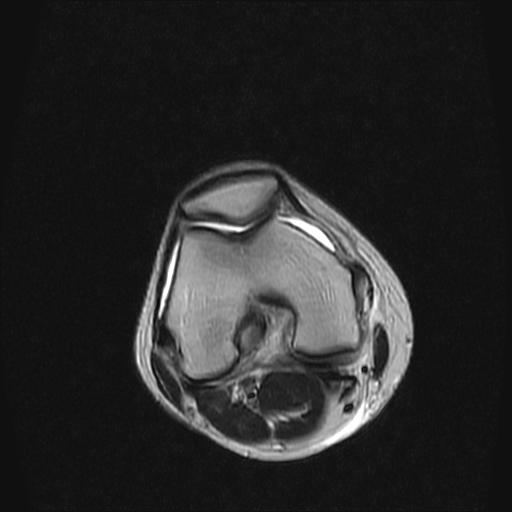

40岁男性,右膝关节外伤,x光平片示,髁间隆突撕脱骨折。

1、前交叉韧带撕裂;

2、外侧半月板后角撕裂;

3、关节腔积液。

半月板1-2级损伤   前交叉韧带撕裂伤   关节腔少量积液  诸骨未见新鲜外伤性改变

髁间隆突撕脱骨折;内侧副韧带损伤。

1、前交叉韧、内侧副韧带撕裂;

3、关节腔积液。4、髁间脊撕脱骨折。

除了关节积液外并无韧带撕裂,acl胫侧附着点有2束,正常情况下脂肪信号。此病例应加做压脂像以便观察是否有骨损伤。